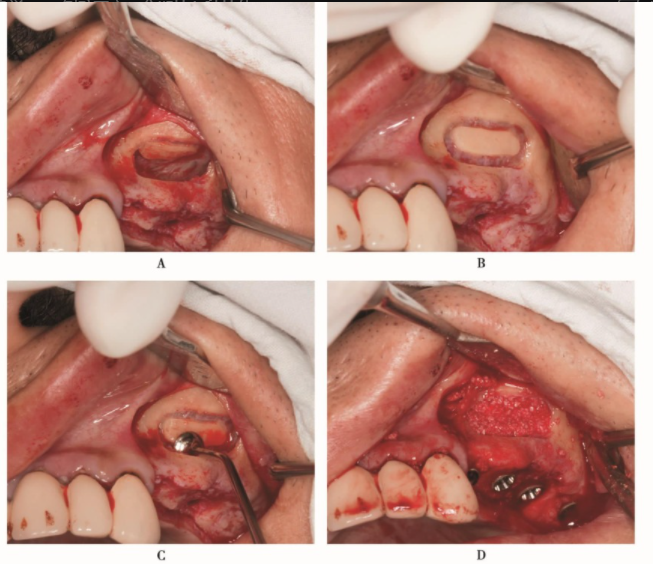

B区完成上颌窦外提升术,并同期植入种植体(图10)。

图10 上颌窦外提升术,同期植入种植体A.采用超声骨刀形成约8mm×15mm大小的窗口;B.分离窦黏膜;C.窦底黏膜已经分离;D.填入骨粉,并同期植入种植体